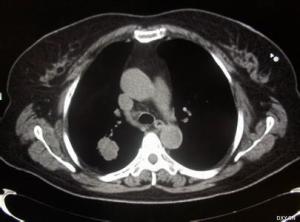

Marie-Bamberger综合征(Marie-Bamberge syndrome)又称肺性肥大性骨关节病、慢性肺性骨关节病、全身性肥大性骨关节病、继发性肺性骨关节病。该综合征首先由Bamberger(1889)报道,翌年Marie又将已经认为是肢端肥大症的患者,依其具有骨变形改变合并有慢性肺部疾病,而另命名为肺性增殖性骨关节病,故此综合征而得名。1963年Berman对本综合征的定义,补充了3条必备的主要征象:杵状指;长管状骨骨端骨膜增殖;关节的肿胀、疼痛和压痛。杵状指在慢性肺部疾患中占18%~33%,而在原发性肺癌可达60%。